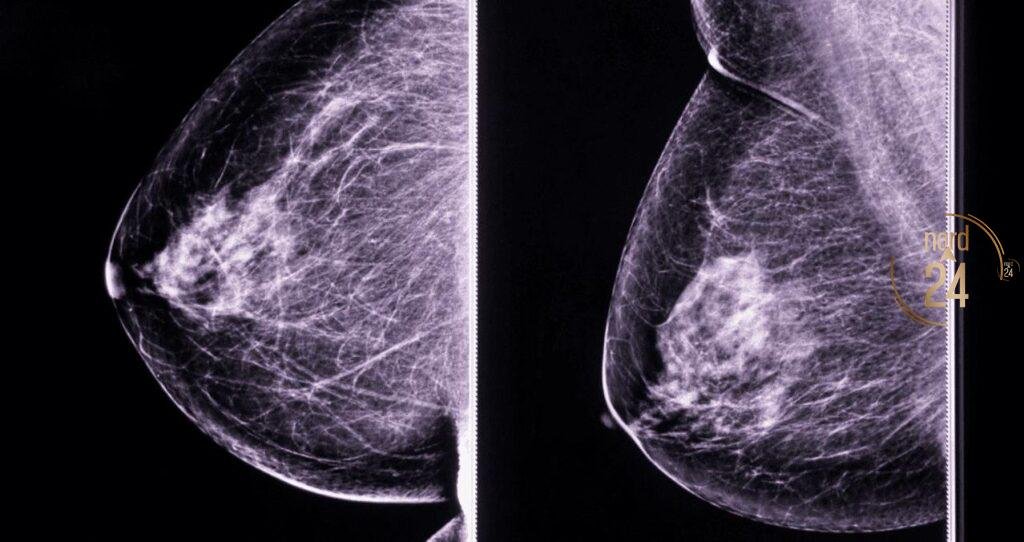

Liliana Velozo, una vecina de 53 años, compartió su valiente testimonio en Radionord tras haber atravesado una cirugía radical de mama derecha hace cinco meses. Durante la entrevista con María Mercedes y su equipo, la paciente detalló los desafíos que enfrenta en su proceso de rehabilitación postoperatoria. Aunque el camino ha sido complejo, Liliana destacó la excelente atención humana y profesional que recibe en el nuevo Instituto Oncológico, donde accede a sus controles y medicación de hormonoterapia sin costo alguno.